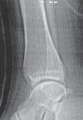

TILLAUX FRACTURES: SALTER-HARRIS TYPE III FRACTURES

1. An anterolateral approach to the ankle is used.

2. This fracture can be fixed by a distal-to-proximal, and anterior-to-posterior, compressive interfragmentary cancellous screw (

TECH FIG 3

).

3. Again, cannulated screw fixation may be used if the surgeon prefers it to the use of noncannulated screws.

22. Crossing the physis is not contraindicated in this fracture pattern because by definition the medial physis is closed and complete physeal closure is imminent.

A B C D

TECH FIG 3•

Tillaux fracture treatment.

A,B.

Tillaux fractures are often not seen clearly on plain radiographic views, and it is important to obtain a mortise view to see the fracture fragment that is obstructed by the fibula in standard AP views.

C,D.

CT scans often aid in fracture characterization and operative planning.

E,F.

These fractures are fixed with compressive interfragmentary cancellous screws across the fracture site, without concern for transphyseal fixation as these patients are always

E F close to skeletal maturity.